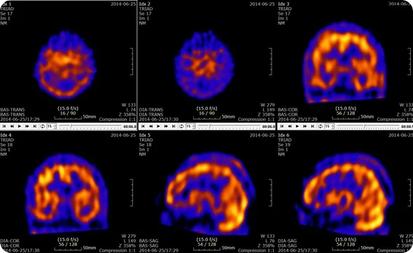

A PET scan can help reveal your tissues and organs’ metabolic or biochemical function Like with SPECT, PET scans use radioactive tracers to show typical and atypical metabolic activity Cancer cells have a higher metabolic activity than normal cells, which makes PET scans useful for cancer detection. PET scans can also be used to detect heart disease and brain disorders like Alzheimer’s and dementia

SPECT scans can detect and monitor the progression of heart disease, such as blocked coronary arteries Coronary arteries supply blood to the heart muscle, and a lack of blood flow can lead to ischemic heart disease, which can cause heart attacks and death Other radiotracers can detect bone diseases, gallbladder disease, and intestinal bleeding SPECT has also been used to help diagnose Parkinson’s disease in the brain and distinguish it from other anatomically comparable movement disorders and dementias As mentioned earlier, PET scans play an important role in cancer detection and heart disease monitoring

Nuclear medicine is a vital field that uses radioactive tracers for detailed diagnostic imaging, providing insights into the health and function of organs and tissues Despite common associations with nuclear weapons and power plants, in medicine, “nuclear” refers to a safe and powerful tool for diagnosing conditions such as, but not limited to, heart disease, bone disorders, Parkinson’s disease, and various cancers Utilizing SPECT and PET scans, nuclear medicine offers unparalleled accuracy in detecting and monitoring these diseases While radiation exposure poses minimal risk, the benefits of precise diagnosis and effective treatment planning far outweigh